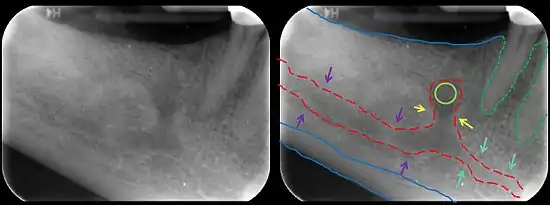

In human anatomy, the mandibular canal is a canal within the mandible that contains the inferior alveolar nerve, inferior alveolar artery, and inferior alveolar vein. It runs obliquely downward and forward in the ramus, and then horizontally forward in the body, where it is placed under the alveoli and communicates with them by small openings.

The mandibular canal is continuous with tow foramina: the mental foramen which opens in the mental region of the mandible and carried the distal fibres of the inferior alveolar nerve as the mental nerve; and the mandibular foramen on medial aspect of ramus, into which the mandibular nerve enters to become the inferior alveolar nerve. The mandibular canal often runs close to the apices of the third molar tooth, and the inferior alveolar nerve can become damaged during removal of this tooth, causing sensory disturbance in the distribution of the nerve. This is sometimes the case for the second or first molar teeth, and care must be taken during removal or root canal treatment in such cases to prevent nerve injury or extrusion of root canal filling materials.[2]

Variations

Several variations of the mandibular canal exist with varying frequency. The most common variant is the retromolar canal (~10 % of canals), whereby a branch is given off in the mandibular ramus which terminates in the retromolar region of the mandible. The retromolar canal may cause bleeding during surgery in the retromolar region such as removal of mandibular third molar teeth. Other variants include a bifid canal with a branch: following the course of the main mandibular canal before re-joining it (forward or buccolingual type); terminating at the apex of a tooth, usually the molar teeth (dental type); opening as an accessory mental foramen.[3] A trifid mandibular canal variation has also been described.[4][5]